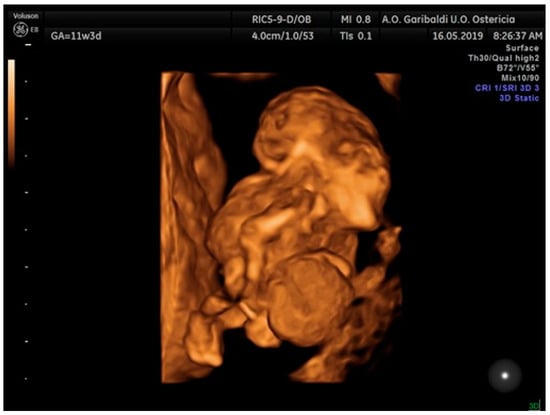

2.2. Case Report 2